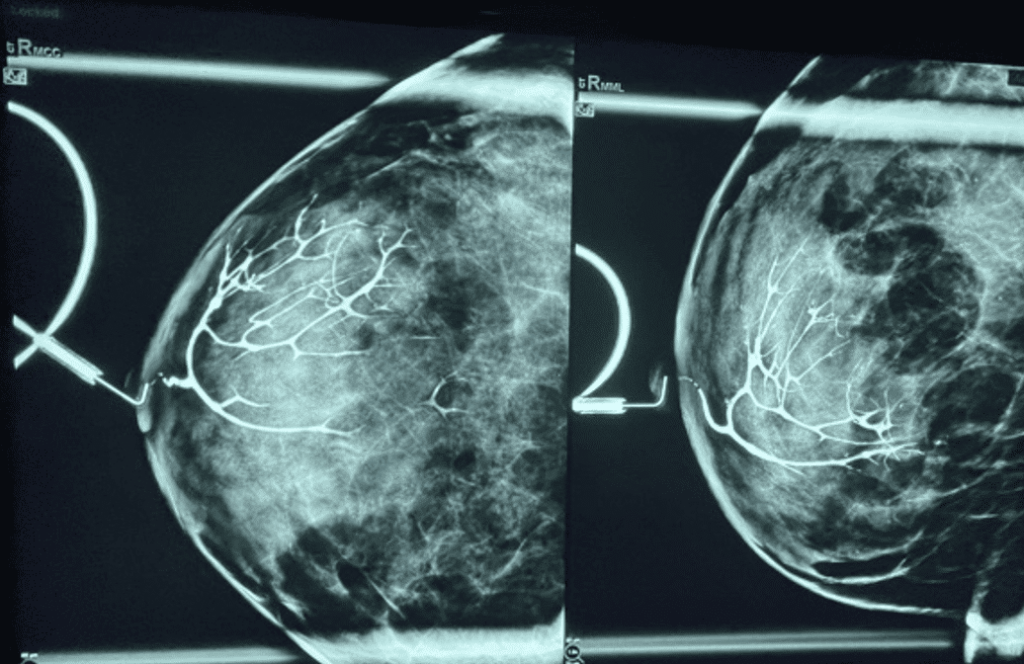

If something doesn’t get better, patients should be evaluated by a physician for an exam and imaging. Temporary issues should resolve within a few hours or day or two. If they persist or get worse, it is important to ensure they haven’t turned into a galactocele (a true milk retention cyst that may require drainage) or another mass is not present in that location. Likewise, mastitis-like symptoms that continue to worsen with ineffective treatments such as massage and pumping may progress to an abscess.

Any “plug” or mass persisting for several days and not resolving with conservative interventions requires referral to a medical provider, who may obtain breast imaging to rule out galactocele and/or other mass.

Galactocele

Galactoceles are true milk-retention cysts that develop most often in the setting of hyperlactation and pumping. Whereas early galactoceles may contain more simple milk, more chronic galactoceles ultimately can develop a collection of extremely thick, semi-solid material. They present with most often a painless swelling in a particular region of the breast and should be confirmed with ultrasound. Patients may be recommended to undergo aspiration, but this almost never resolves the collection and it refills quickly. They are drained as above.